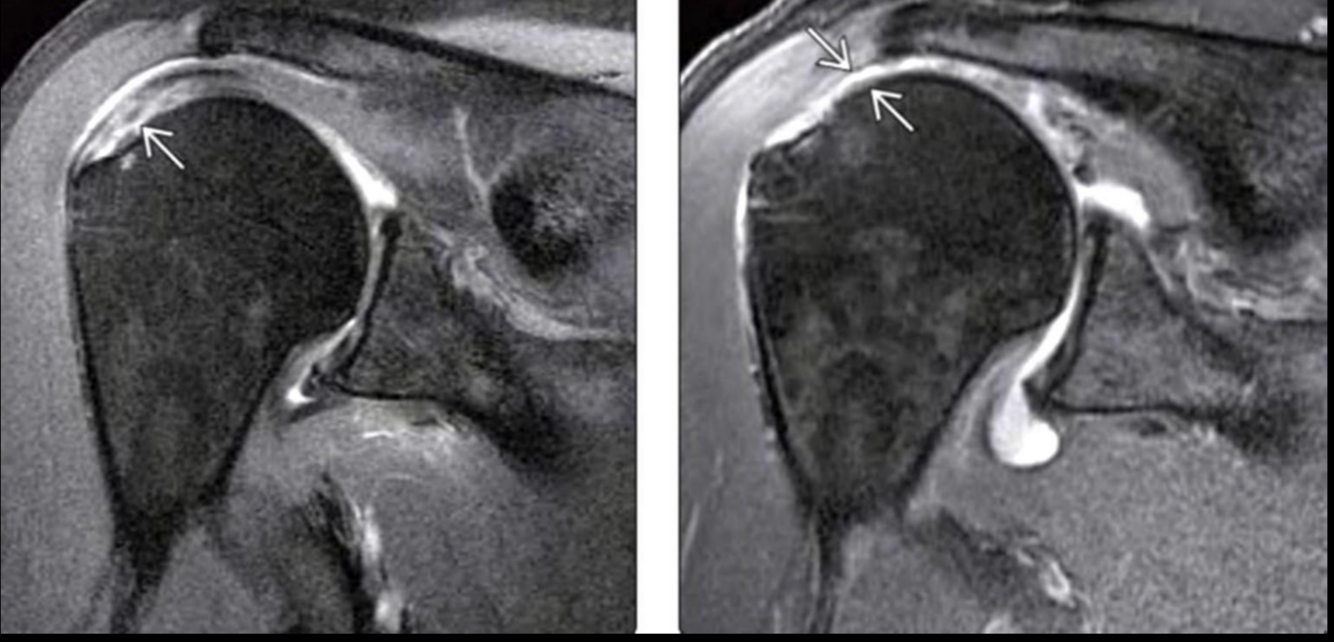

A

Rotura tendon supraespinoso

Hiperintenso en T2

Detecta lesiones asociadas y desgarros pequeños

RM manguito rotador

Normal

Desgarro del manguito